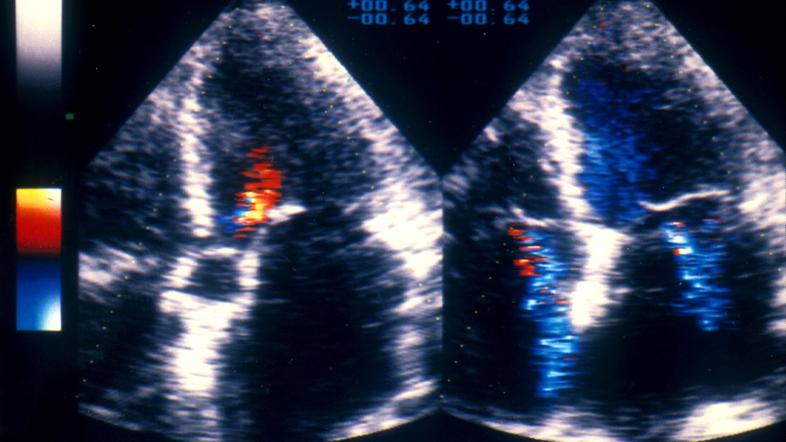

Srčno popuščanje

Nezdravo za srce